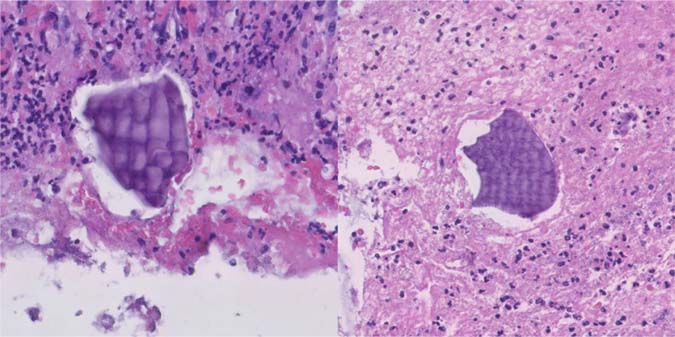

Figure 6: High power images of fibrinopurulent exudate and embedded Kayexalate crystals with purple color and typical fish-scale pattern (Hematoxylin and eosin, 20× magnification).

Figure 7: High power images of fibrinopurulent exudate and embedded sevelamer crystals with yellow color and fish-scale pattern (Hematoxylin and eosin, 20× magnification).

Figure 8: High power image of Kayexalate (left) and sevelamer (right) crystals with differential staining patterns (Kinyoun, 20× magnification).

Table 2: Comparison of medical resin appearances in histologic sections.

Features Sodium polystyrene sulfonate Sevelamer

Brand name Kayexalate Renagel, Renvela

Mechanism of action Potassium-binding agent Phosphate-binding agent

Shape Rectangular Rectangular

Texture Fish scales Fish scales

Hematoxylin and eosin Purple Pink (center), yellow (edges)

Kinyoun stain Black Magenta

Source: Adapted from Gonzalez (28).